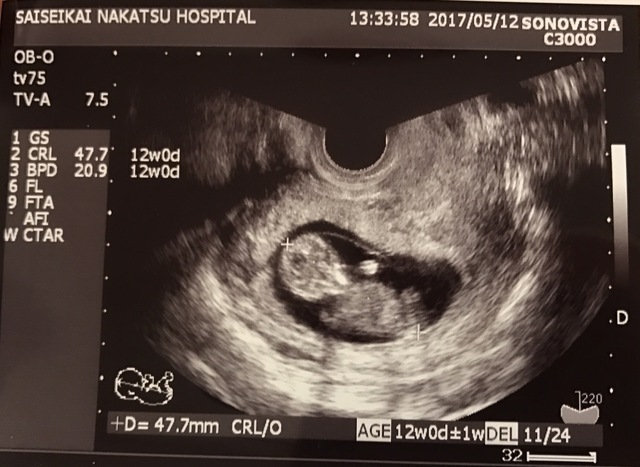

11週0日(11w0d・性別不明)|sumire0113 さん(35歳)

エコー写真撮影時のエピソード:

九州から関東への引越し後初めて新しい病院で撮ったエコー写真です。

今までのエコーから腹部エコーに初めて変わり、先生も大笑いするくらいに、ぐるんぐるんと動き回っている姿を見て感動しました。

まだつわり真っ只中だったので、これでまだ頑張れると勇気をもらいました。 そんな我が子、エコー写真を撮る瞬間にピースをしてくれた瞬間です。